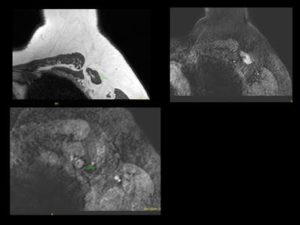

1. Irregular mass with spiculations and microcalcifications in supra-areolar region of left breast – BIRADS 5. 2. On MRI – Irregular enhancing mass with surrounding extensive clumped and nodular enhancement in ductal distribution in upper quadrant- representing multifocal DCIS or extensive ductal spread. 3. Thickening in left axillary lymph nodes- likely metastaticCortical

1. Invasive ductal carcinoma with multifocal DCIS / extensive intraductal spread. 2. MRI changes the management from Breast conserving surgery to MRM because of extensive intraductal component other then mass.

MRI of the breast is recommended in patients who are diagnosed with breast cancer before surgery for treatment planning as it is more accurate for the the suze of the lesion, tells about multifocal disease, contralateral breast cancer and lymph node staging. The management can change from lumpectomy to mastectomy. However use of pre-operative MRI in all cases is still debatable.